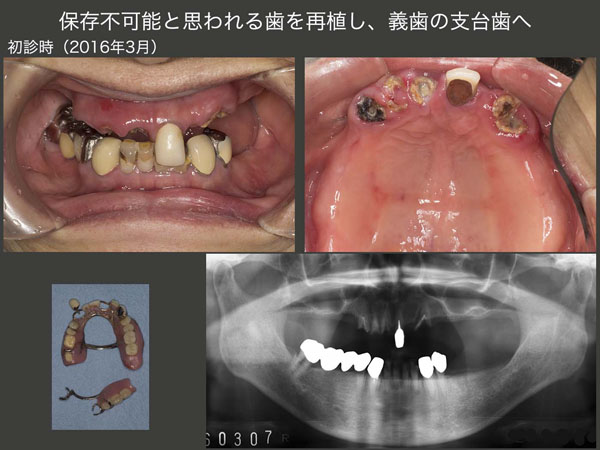

7.保存不可能と思われる歯を再植し、義歯の支台歯へ

2016年3月初診,79歳女性.右上3の冠がコアごと外れ,義歯が安定しなくなったとのことで来院.上顎においては残存歯をすべて抜歯し,総義歯にする選択肢があった.顎堤が優型であり,総義歯でも十分機能すると思われたが,口蓋を被うことになるので,異物感や発音障害が生じる可能性も考えられる等を説明したところ,患者さんはできるだけ歯を残して欲しいと希望した.

まず右上3の増歯を行い,つぎに同部の感染根管治療を行った.その後,暫間のOPAアタッチメントを装着し,義歯の維持を担ってもらった.なお,アタッチメント根面板の所に保持を設け,ワイヤーを固定できるように細工しておいた.

以上の準備が整ったところで,2016年6月に右上3および左上1を固定源として,右上1,2および左上3の再植を同時に行った.この際,歯肉縁上歯質が得られるところまで挺出し,ワイヤーに固定した.

デンタルX線写真は,術後2ヵ月半の状態であるが,右上2の動揺は収まらなかった.また左上3の遠心に7mmの歯周ポケットが残ったため,同部の歯肉切除を行った.